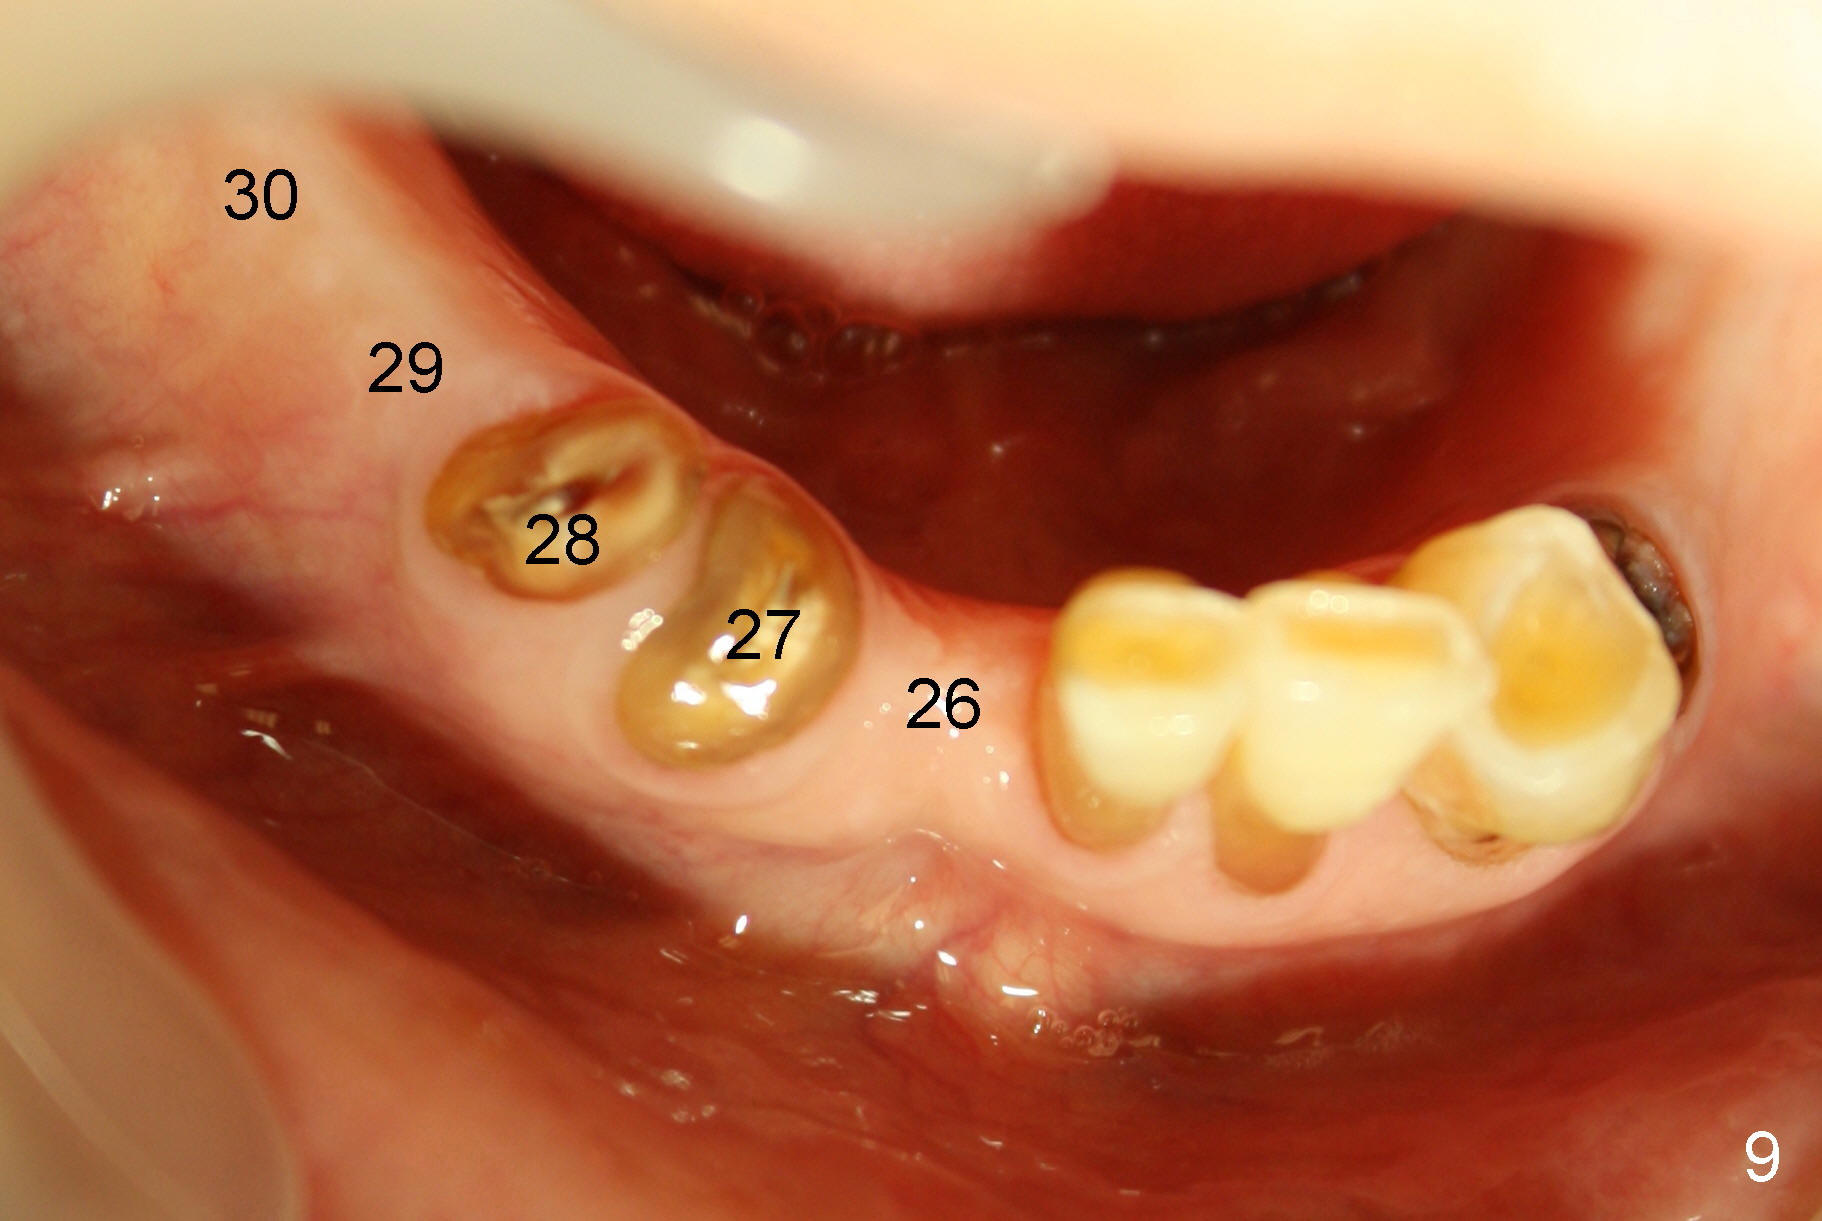

A 85-year-old man has poor dentition (Fig.9). Multiple implants are to be placed at one or two stages (#26-30). If primary stability is obtained for individual implants, they are splinted and immediate provisional is fabricated.

Fig.1-3 are CBCT sagittal sections of the lower right quadrant, whereas Fig.4-8 are coronal sections. The lower left quadrant has been restored.

The sockets of #27,28 will be treated with 2% Xylocaine/1.:50,000 Epinephrine as control group of the antibiotic study.